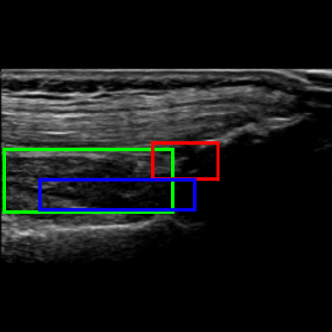

Considering the detection problem, Figure 10 shows US images where the two approaches detected the SQR with the lowest and the highest IoU. In Figure 10a, the Multi-task approach wrongly detects as SQR an image region that is similar to an actual SQR in terms of position and shape, resulting in a very low value of IoU (0.330.330.33). In this case, also the Detection approach can not reliably detect the right target precisely, and indeed it detects only a small portion of the actual SQR (IoU=0.330.330.33). Instead, in the example shown in Figure 10b the Multi-task approach accurately detects the SQR (IoU=0.950.950.95), while the Detection approach identifies the same area with a lower IoU (0.68)0.68).

Figure 10c shows the US image for which the Detection approach provided the lowest IoU value. The problem is similar to that of Figure 10a: a region is erroneously recognized as a SQR because it is similar to a SQR. In this case the detected bounding box does not overlap with the ground truth, hence the IoU is zero. Instead, the Multi-Task approach basically detects the right target (IOU=0.580.580.58).

Refer to caption

(a) Worst detection by Multi-Task approach

(b) Best detection by Multi-Task approach

(c) Worst detection by Detection approach

(d) Best detection by Detection approach

Figure 10: Detection examples. Green represents the ground truth, red and blue the results of the Multi-Task approach and Detection approach, respectively.

Figure 10d shows instead the US image for which the Detection approach provided the highest IoU value (0.960.960.96). In this case the Multi-task approach identifies the right target less precisely, resulting in a IoU of 0.550.550.55.